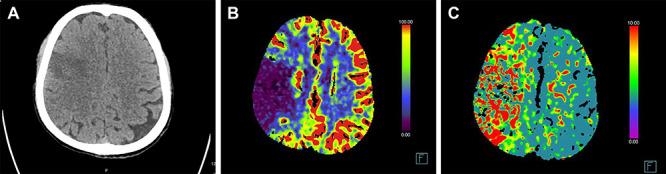

Most cases of stroke associated with coronavirus disease 2019 (COVID-19) occur during the course of a characteristic COVID-19 respiratory illness. We report three patients where the presenting feature of COVID-19 was stroke. Two patients had no respiratory symptoms throughout their clinical course. In each case, COVID-19 was confirmed by a reverse transcription polymerase chain reaction (RT-PCR) test and the diagnosis of ischaemic stroke by brain imaging. The patients were relatively young (40, 45 and 50 years). None had a prior history of cerebrovascular events. Stroke risk factors were absent in one, limited to overweight and smoking in another but more prominent in the third patient. Two patients had large vessel occlusion and elevated D-dimer levels. Multiple infarcts were seen in two patients. Clinicians should consider the possibility of COVID-19 in patients presenting with stroke and conversely consider investigating for stroke if a patient with COVID-19, even if mildly ill, develops acute neurological symptoms.